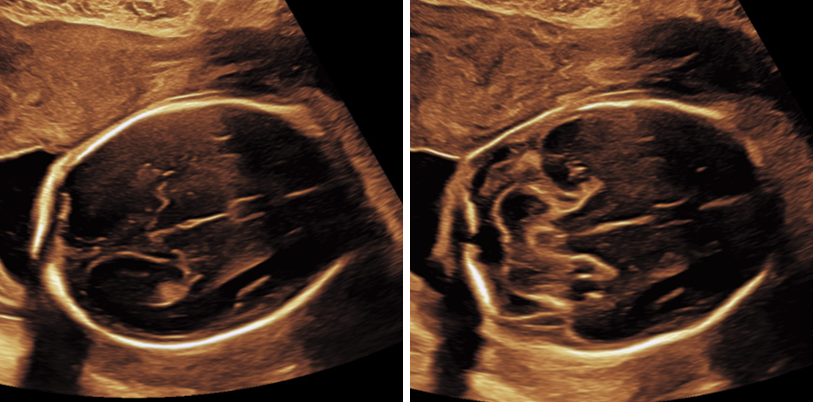

Ersttrimester-Screening: 12-13 SSW

In diesem detaillierten Ultraschall können wir neben der Nackentransparenz bereits die vollständig angelegten Organe Ihres Kindes untersuchen. So erhalten Sie schon früh einen bildlichen Eindruck der ersten Entwicklungsschritte.